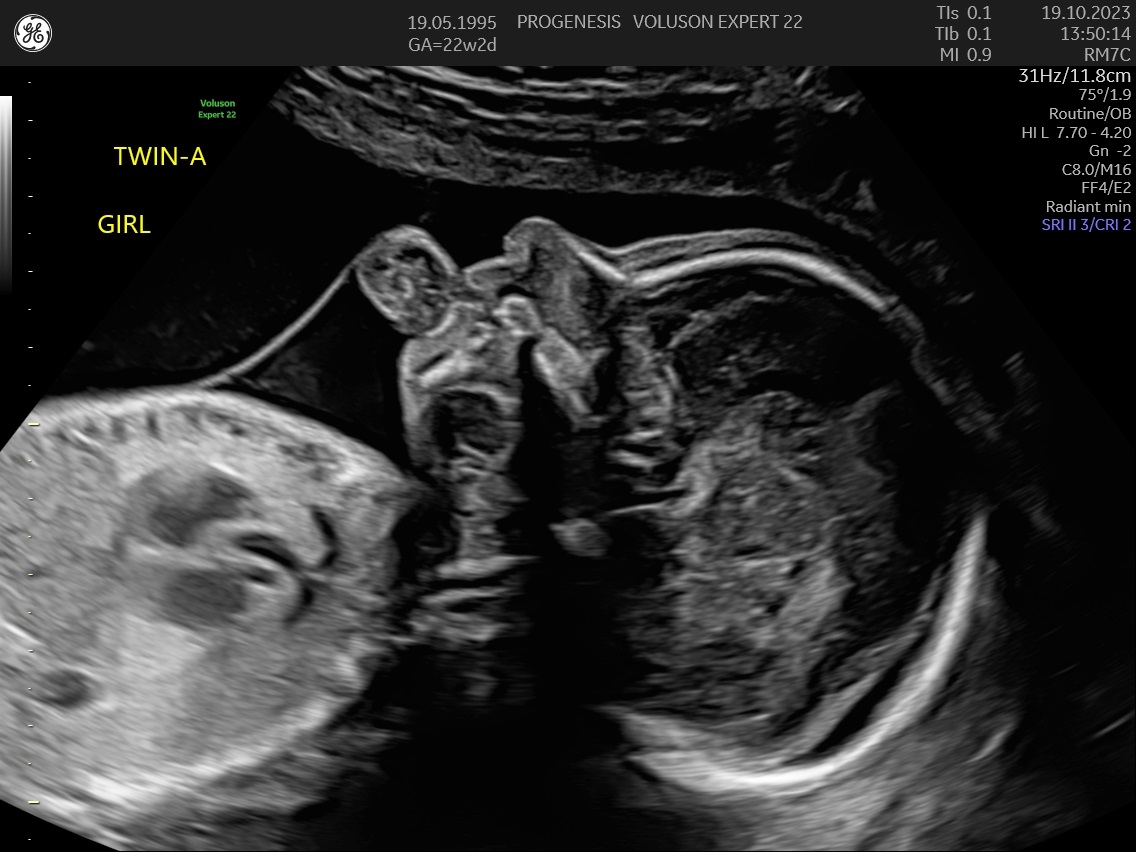

α) Η λεπτομερής αξιολόγηση της εμβρυϊκής ανατομίας, όπου αναγνωρίζονται τυχόν ανατομικές ανωμαλίες.

γ) Ο έλεγχος της ανάπτυξης του εμβρύου, του πλακούντα, του ομφαλίου λώρου και του αμνιακού υγρού.